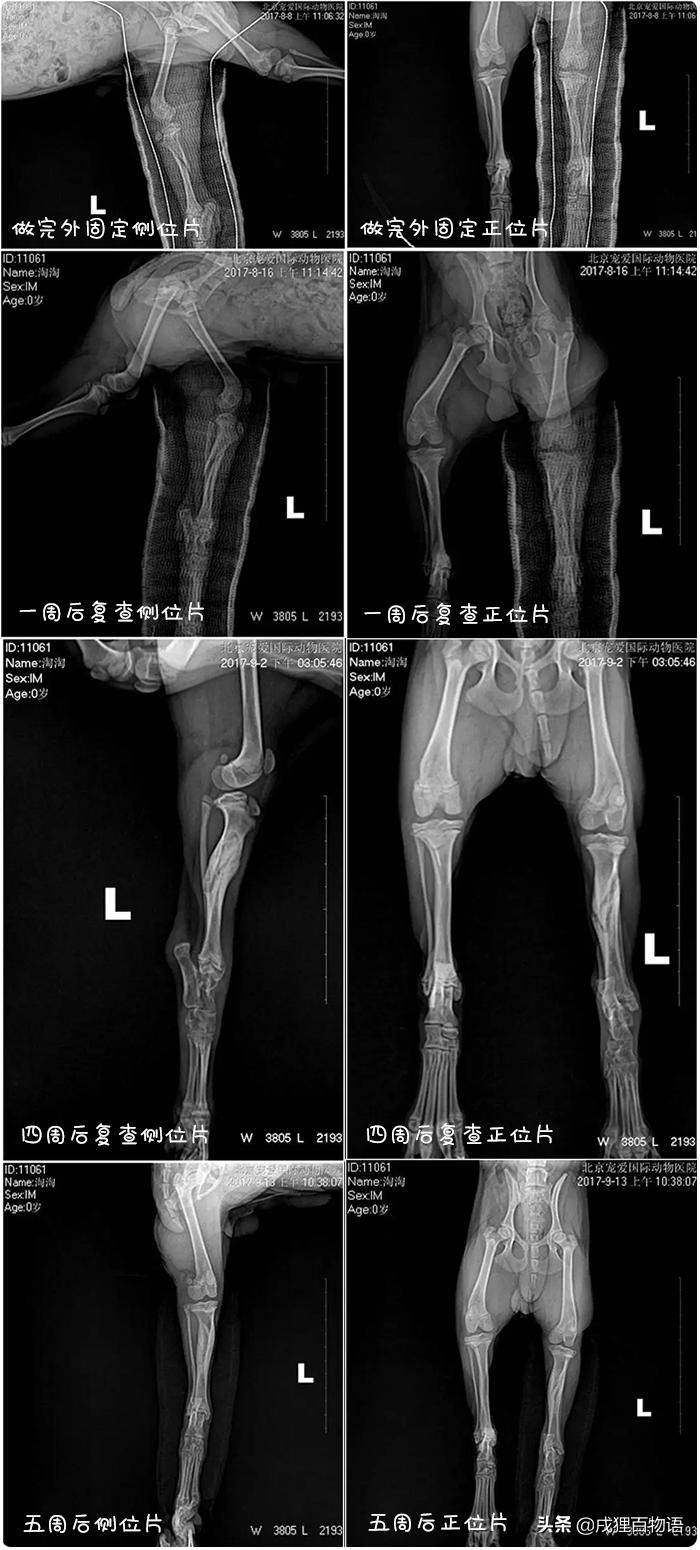

用玻璃纤维左后肢完全缠绕骨折外固定

化验:DR显示左后肢不完全骨折

左后肢胫骨不完全骨折